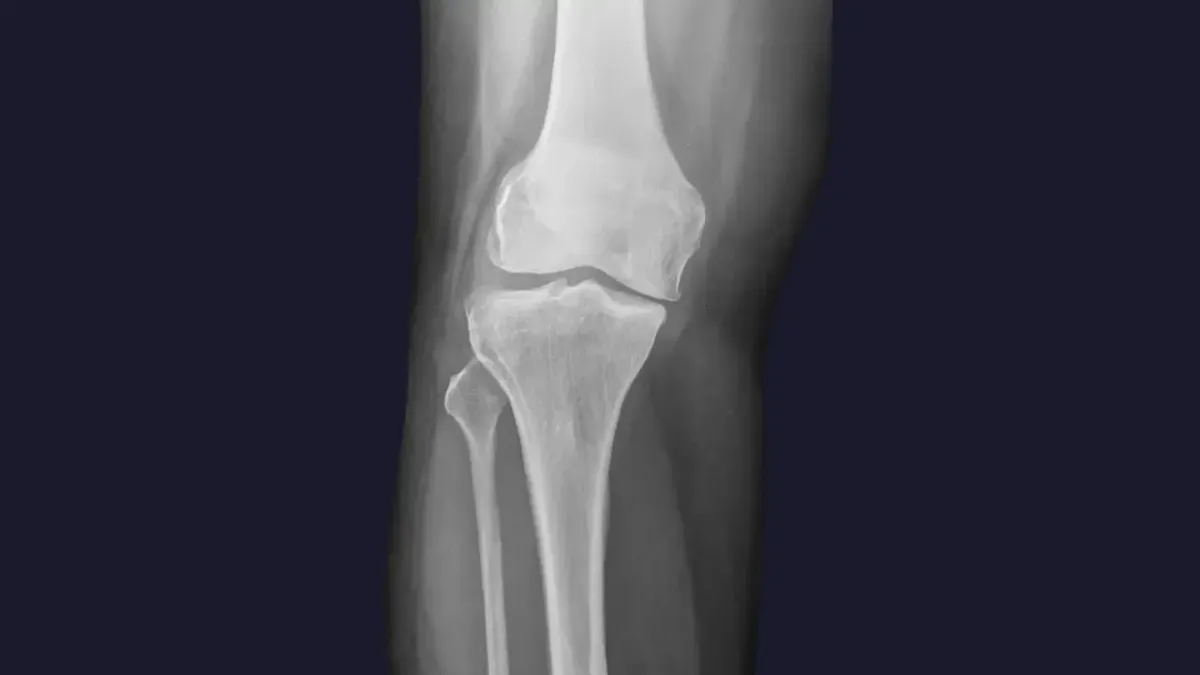

Knee pain is a widespread complaint, often stemming from a variety of sources. Here are some of the common culprits we see in Cincinnati, OH :

Misalignment: Even subtle misalignments in the knee joint itself, or in the hips and pelvis, can lead to improper tracking of the kneecap, increased wear and tear, and pain.

Arthritis: Degenerative changes in the knee joint can cause stiffness, swelling, and chronic pain.

Ligament or Meniscus Issues: While severe tears may require surgical intervention, chiropractic care can help manage pain and improve function for less severe injuries by optimizing joint mechanics and supporting the healing process.

Poor Biomechanics: Imbalances in the muscles surrounding the knee, or issues with foot mechanics, can place excessive stress on the joint.